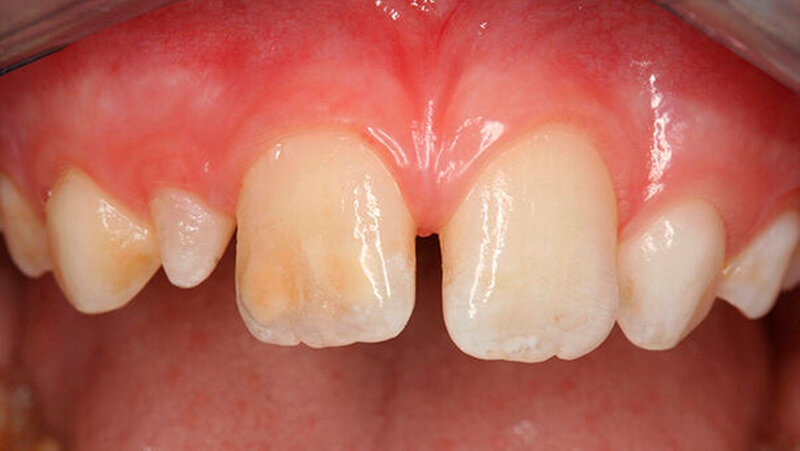

Bei einigen Patienten bestand allerdings auch schon im Milchgebiss eine Neigung zu Hypomineralisationen (Abbildung 3), klassifiziert wurden diese inzwischen als MDH (=deciduous molar hypomineralization) [Elfrink et al., 2012]. Inwiefern eine Hypomineralisation im Milchgebiss aber tatsächlich einen Indikator für eine MIH im bleibenden Gebiss darstellt, ist bisher nicht genauer zu beschreiben [Elfrink et al., 2012].